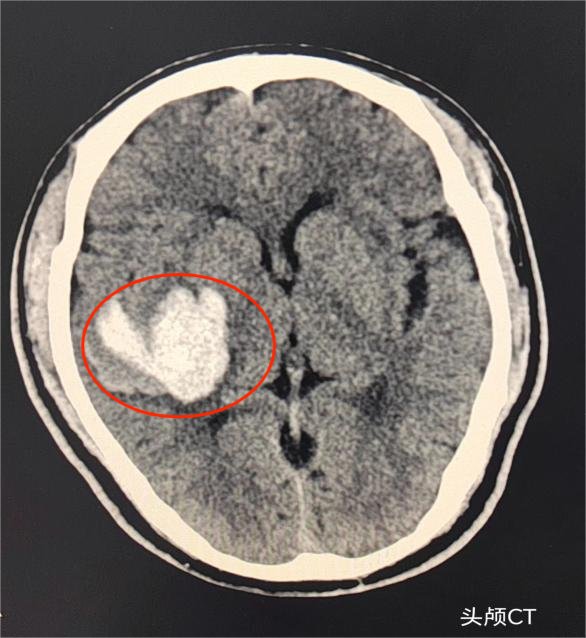

中风患者CT检查发现右侧大脑球出血,同时进行头颈部动脉血管造影检查。